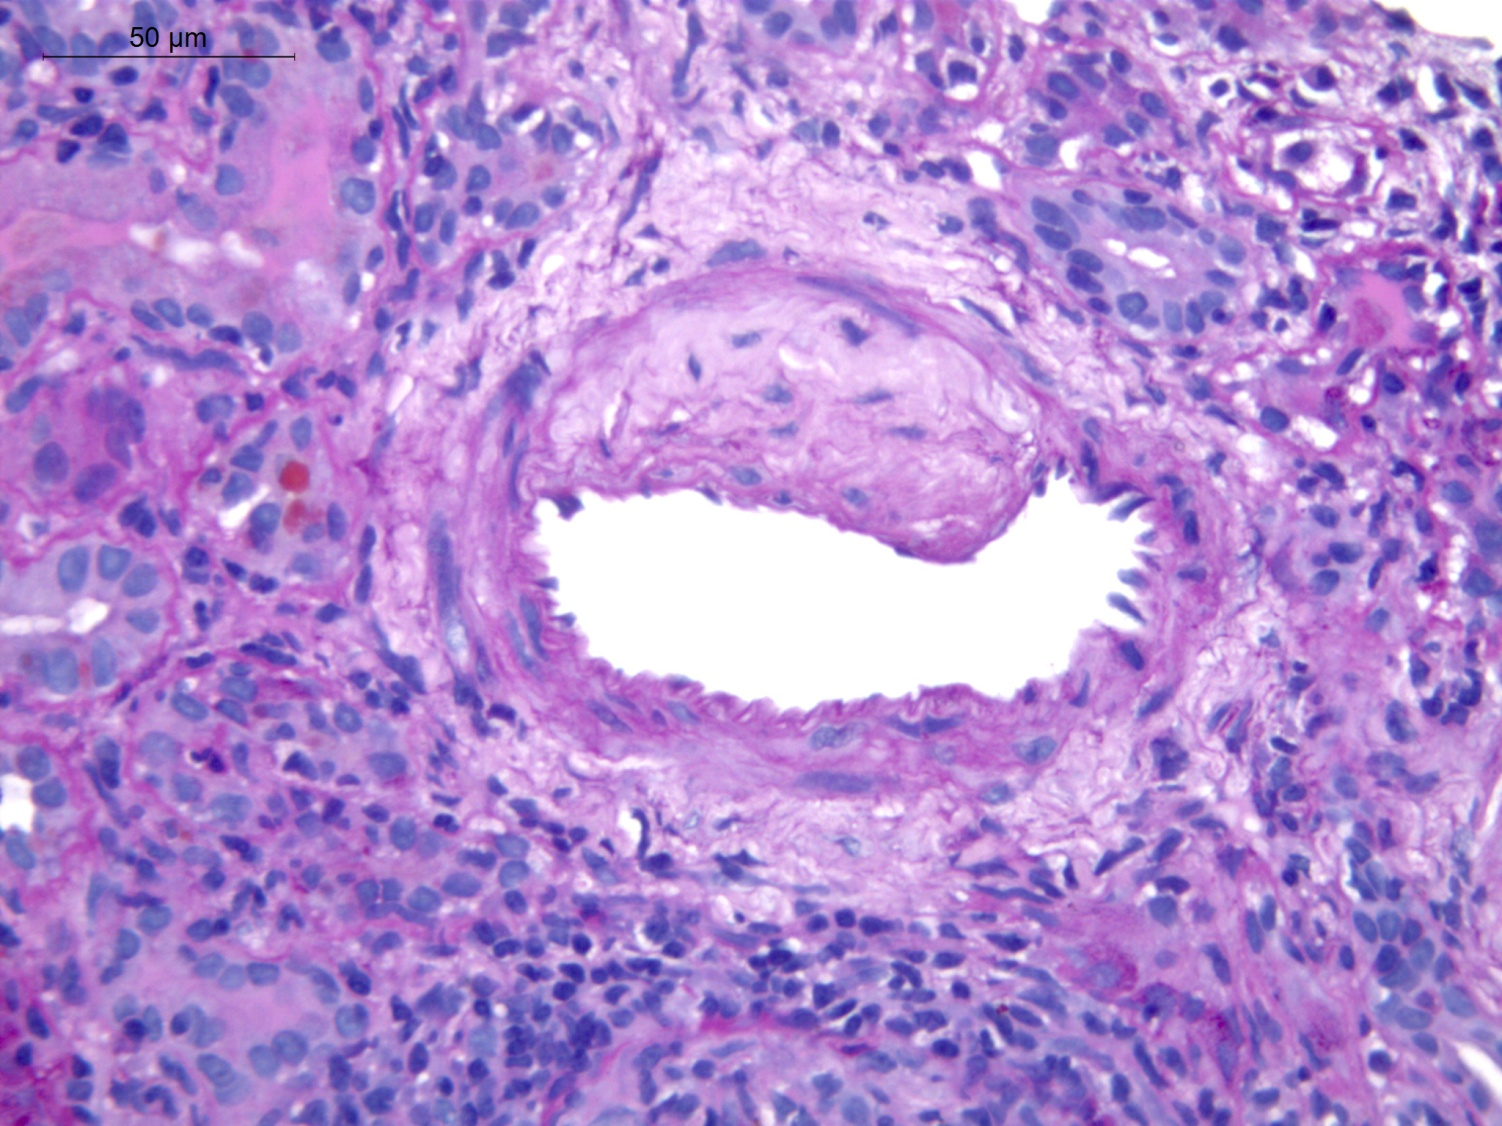

Figure 1 Glomerulus (H&E stain) showing cellular crescent (extracapillary proliferation) with ruptured Bowmans capsule(arrow) and periglomerular infilammatory infiltrate.

Anti-GBM disease of pregnancy is uncommon with its incidence being restricted to case reports. Crescent formation is the histopathologic hallmark of Anti-GBM disease with almost 95% of patients having evidence of crescent formation on kidney biopsy and in 80% of these patients more than 50% of glomeruli will be affected.10 The proportion of crescents has been observed to correlate strongly with the degree of renal impairment at presentation.